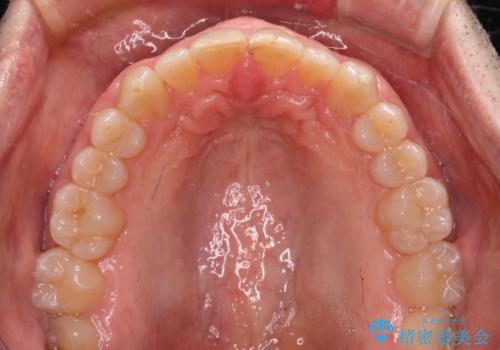

- 前歯のデコボコを気にして来院された患者様です。

インビザラインでもワイヤー装置でも対応可能でしたが、仕事の都合で来院回数を減らしたいとのことでインビザラインによる矯正治療を選択されました。

著しく咬合力が強いため、奥歯がしっかりと噛めずに治療が長引くことが懸念されました。

1セット目のインビザラインを使用した際には左右ともに大臼歯が咬み合っていなかったのですが、2セット目できっちりと仕上げることができました。